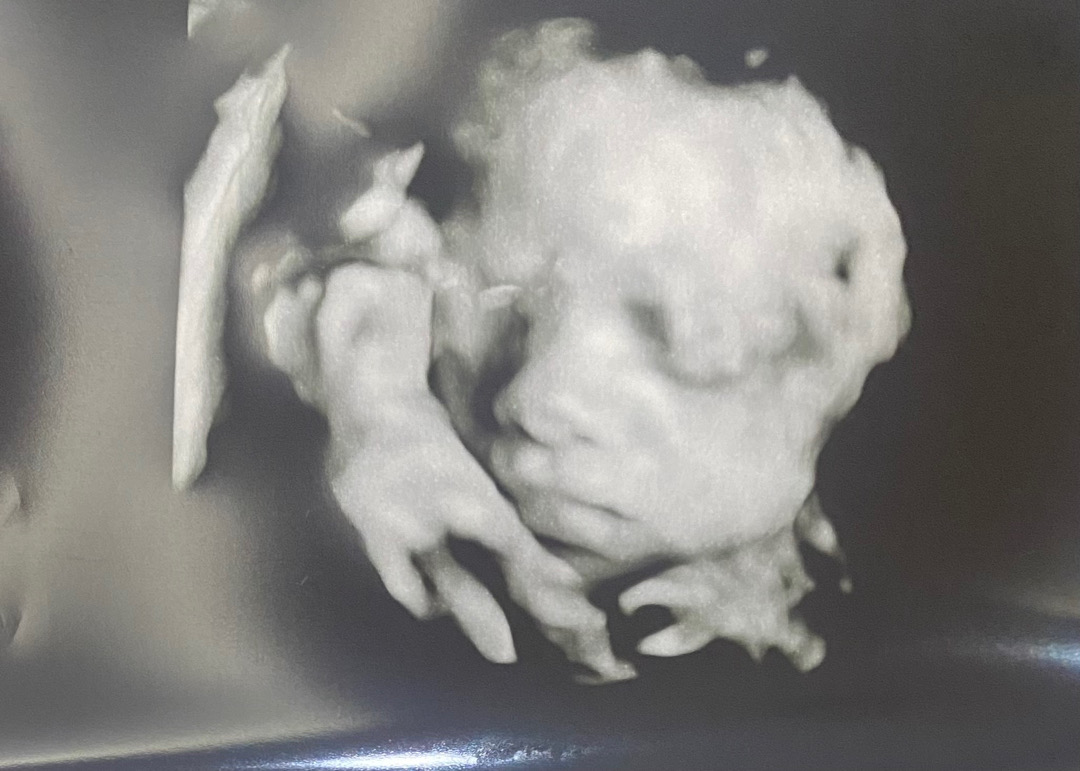

26주차 입체초음파랑 임당검사 하구왔어요 ㅎ

체중이 많이 나가서 임당검사 많이 걱정했는데 무사히 통과했어요 ㅎㅎ 5월 베동님들 입초시기라 다른 애기들 사진 많이 봤는데 모두 애기애기 해서 귀엽던데 뭔가 애기스럽지 않은 외모에 살짝 당황하구 왔네요 그래도 엄마라 그런지 너무 귀엽네여 😆